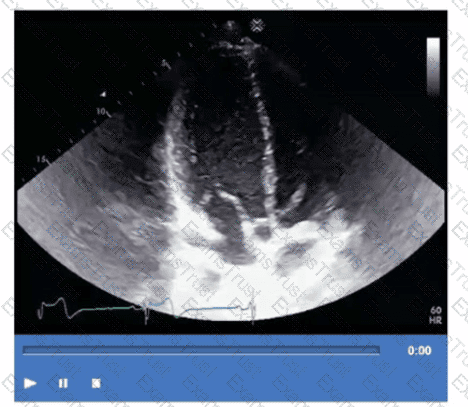

Which adjustment should be made to optimize this video?